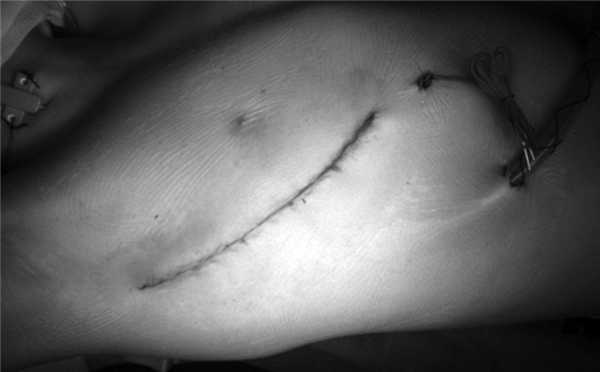

8) правая плевральная полость дренируется в шестом-седьмом межреберье. Послеоперационная рана закрывается (см. рисунок, г). Рисунок 1. Этапы операции при выполнении переднебоковой правосторонней торакотомии. г - послеоперационный шов.